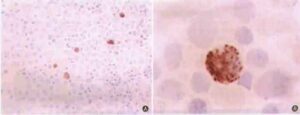

IL-18